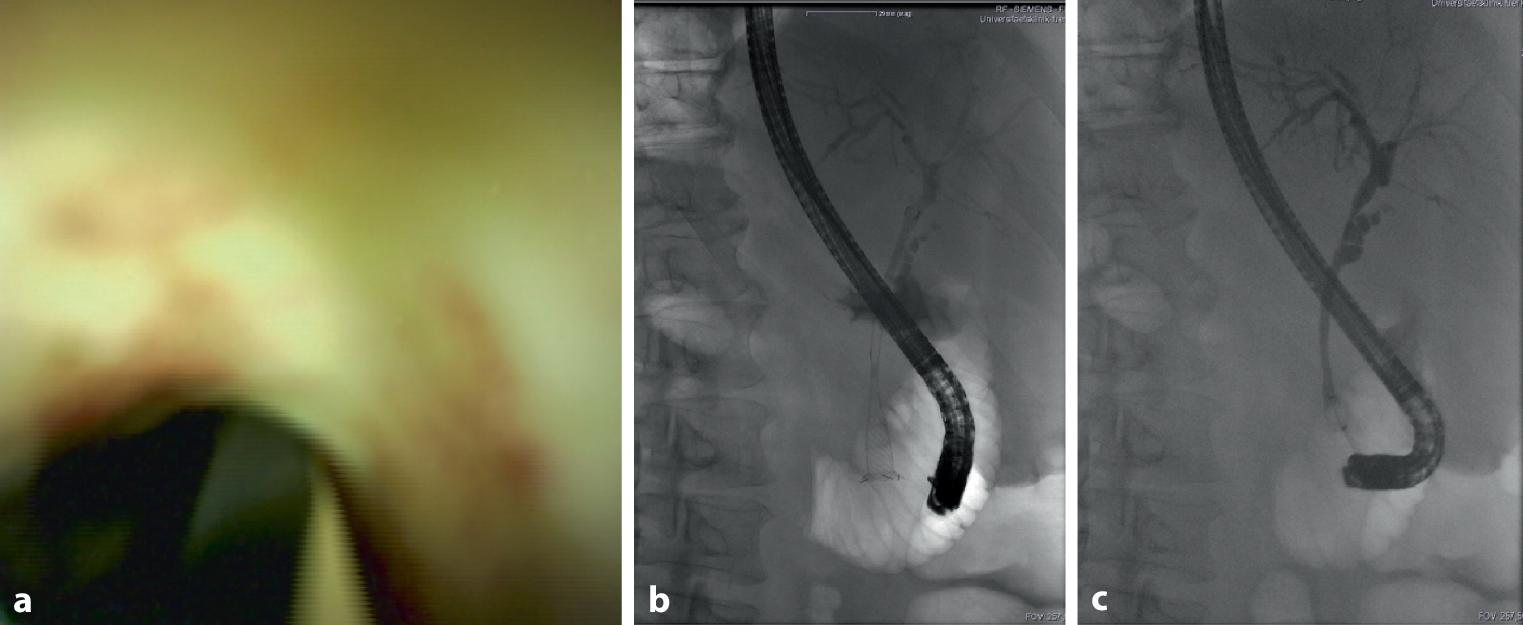

Patient 2 was admitted from a primary care hospital due to lung failure and for evaluation of ECMO therapy. The latter was refrained from as a consequence of a prolonged course of COVID-19 and a limited prognosis regarding rehabilitation. At the time of admission, liver chemistries were already elevated. Imaging and ERCP with cholangioscopy displayed ischemic cholangiopathy similar to patient 1. A fully covered self-expanding Wallstent (Wallflex, Boston Scientific, diameter 10 mm, length 80 mm) had to be inserted to stop diffuse bleeding of the major duodenal papilla 3 weeks after initial ERCP. The stent did not expand to more than 4 mm (Fig. 2).

Fig. 2

Similar to patient 1, cholangioscopy in patient 2 showed an irregular and ischemic pattern of the biliary mucosa (a); after stent-implantation, the common hepatic duct did not expand more than 4 mm (bc)